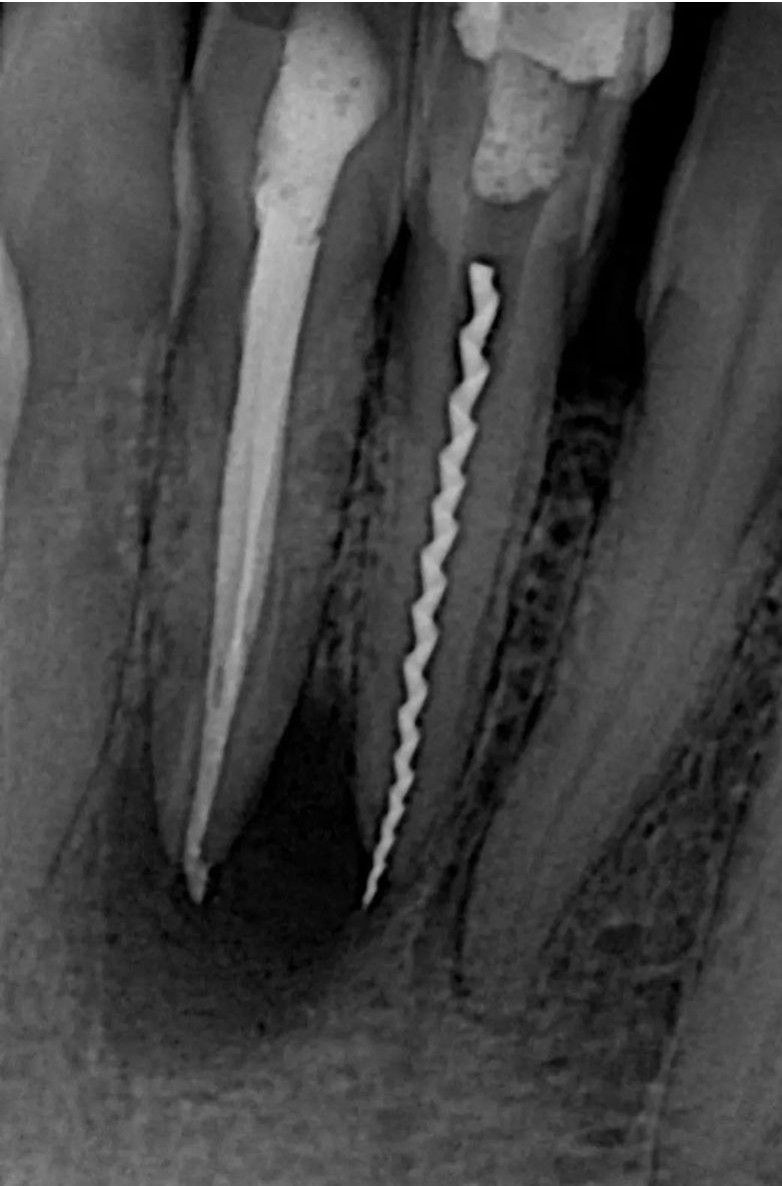

Tough Case to Retrieve

The file just broke!